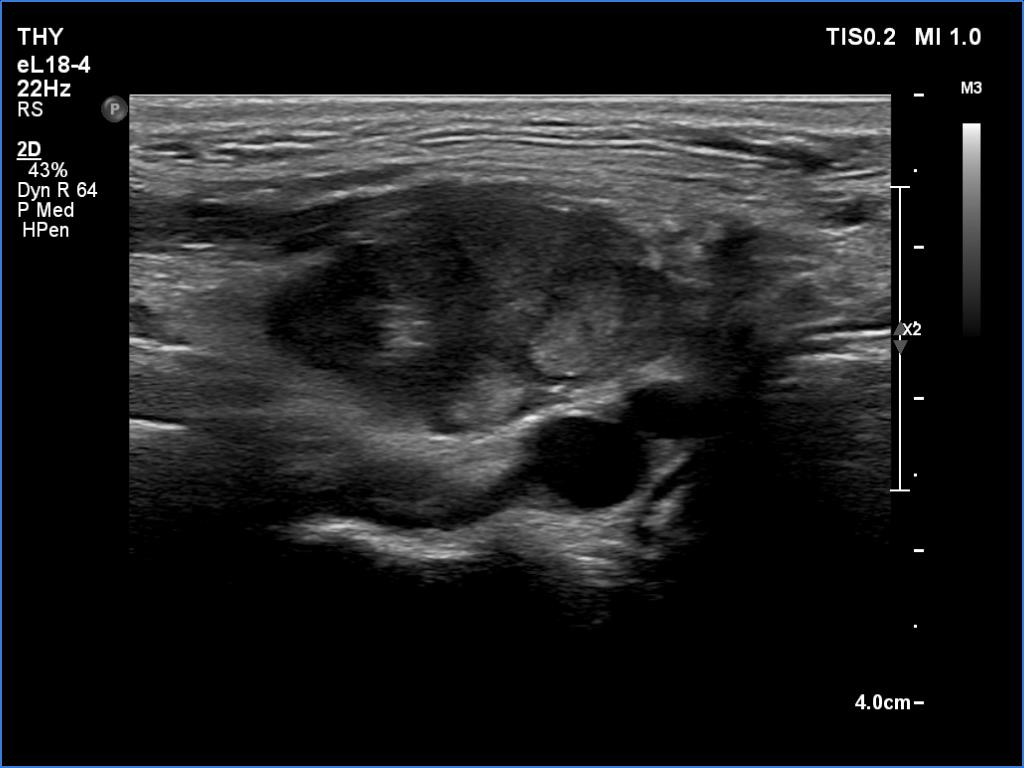

According to the palpable mass in the right submandibular area, there was a heterogeneous lesion which has hypoechoic and echonormal parts. The mass had irregular margins and showed vascularity. The distance between the submandibular mass and the thyroid was more than 35 mm.